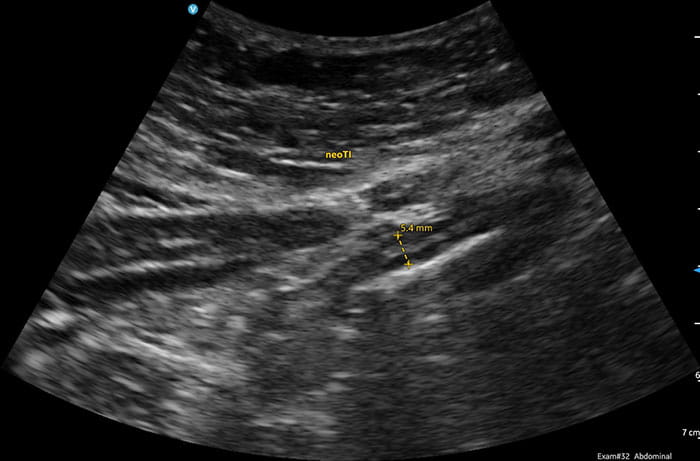

“The use of ultrasound in patients with IBD is fairly new in the U.S.,” Dr. Nguyen says. “In the past, we have only used ultrasound to look at the gallbladder and the liver, not the intestine or the colon. Now, we are using it in patients with IBD to look for signs of inflammation, to manage treatment and to diagnose other gastrointestinal complications such as diverticulitis, bowel obstruction and appendicitis.”

In addition to diagnosing IBD and other GI conditions, intestinal ultrasound can be used post-surgery to proactively identify potential complications, such as pockets of infection, he adds. Studies have shown that ultrasound is accurate in diagnosing IBD and monitoring response to treatment.